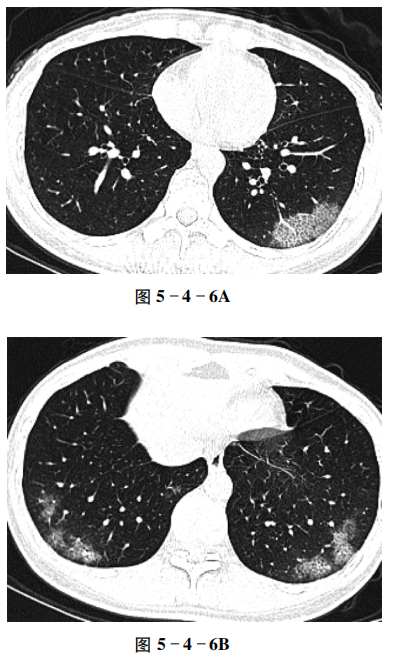

例6 新型冠状病毒肺炎(多发)

【病史摘要】 女性,38岁。因发现肺部感染6天,发热4天入院,有新型冠状病毒肺炎患者接触史。

【CT征象】 CT平扫示两肺下叶胸膜下多发大小不等斑片状磨玻璃影,以后、外基底段为主,部分病变融合,小叶间质增厚,可见铺路石征(图5-4-6A、B)。

【重要征象】 胸膜下分布,磨玻璃影,小叶间质增厚,铺路石征。

【CT拟诊】 ① 新型冠状病毒肺炎(COVID-19)。② 其他病毒性肺炎。③ 支原体肺炎。④ 真菌感染。

【最终诊断】 新型冠状病毒肺炎(COVID-19)。